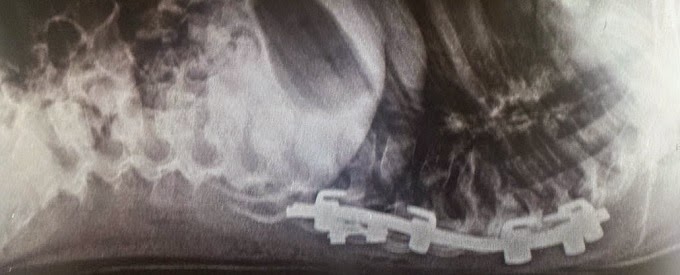

Es un paciente masculino de 14 años, al estar realizando actividad deportiva presenta una contusión directa de baja intensidad sobre la cadera izquierda, refiriéndose imposibilidad para la deambulacion por lo cual es llevado para su valoración, se toman estudios radiográficos

En donde se encuentra solución de continuidad en región subtrocanterica, además se observa lesión expansiva desde la región subtrocanterica hasta cuello de cadera por lo cual se inicia protocolo para lesiones tumorales oseas, se realizan estudios de laboratorio. TAC

Se lleva a cabo manejo quirúrgico de la misma por medio de legrado óseo de la lesión, crioablasion con óxido nitroso, aplicación e injerto homologo y ostwosintesis con dhs

A 8 meses con buena integración de injerto y consolidación de fractura

Con apoyo completo de la extremidad e incorporado a sus actividades habituales el paciente.